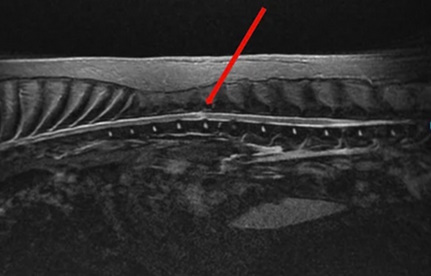

MRI σπονδυλικής στήλης σκύλου. Οβελιαία τομή. Το κόκκινο βέλος δείχνει τη βλάβη του νωτιαίου μυελού, η οποία εμφανίζεται με σήμα αυξημένης έντασης στην ακολουθία Τ2 και εντοπίζεται ακριβώς πάνω από το μεσοσπονδύλιο διάστημα Θ13–Ο1.